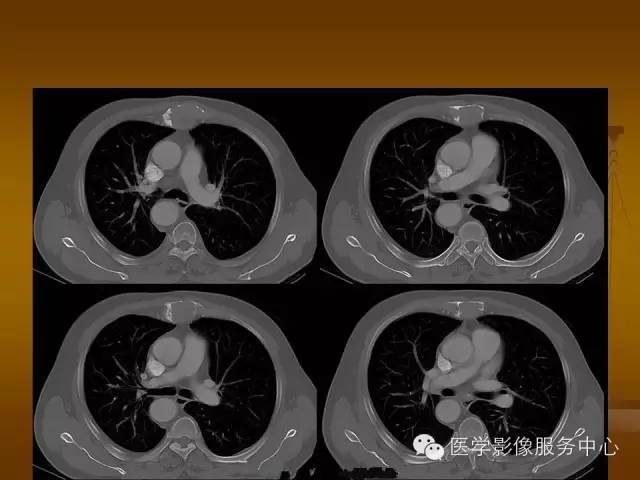

胸骨浆细胞骨髓瘤1例CT影像表现

特征性穿凿状、鼠咬状及蜂窝状骨质破坏,边缘清楚,骨质疏松,病理性骨折及软组织肿块等表现,骨质硬化及骨膜反应少见。

骨质破坏区完全为软组织取代,骨质膨胀,边界清楚,常突破骨皮质形成软组织肿块。

增强扫描可见病灶轻中度强化,一般于静脉期达峰值。